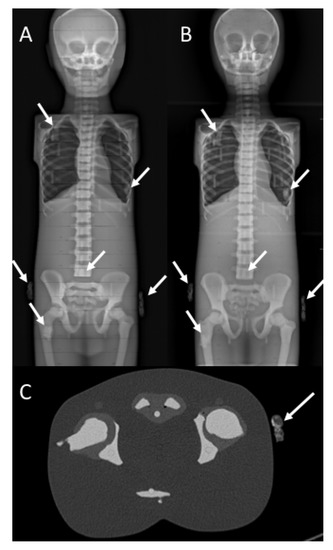

By applying different image scanning speeds, the radiation dose delivered was progressively and significantly lower for the EOS-Fast protocol (KAP 258.6 mGy cm2) compared with the EOS-Medium protocol (KAP 387.89 mGy cm2, p < 0.001), and even more when compared with the EOS-Slow protocol (KAP 517.19 mGy cm2, p < 0.001) (Figure 2). Moreover, the EOS-Fast radiation dose was also significantly lower than the median radiation dose of conventional radiographs (644.7 (599.4–651.97) mGy cm2, p = 0.004) for all phantom configurations (Figure 3). Figure 4 shows a case from this study.

Figure 4. EOS (A), CR (B), and CT (C) images of a phantom with six inserts (arrows).